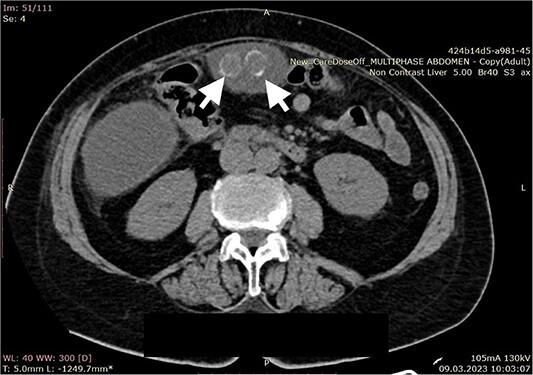

以巨大胆汁瘤为首发表现的胆囊穿孔:1例病例报告及文献复习

Large biloma as the initial presentation of gallbladder perforation: a case report and literature review.

Biloma is an encapsulated intra or extra-hepatic collection of bile after biliary tree trauma. Post-procedural and traumatic biliary damage are the most common etiologic causes. Gallbladder perforation due to acute cholecystitis rarely presents with biloma occurrence. We present a case of large extrahepatic biloma formation as a consequence of a perforated gallbladder.

胆汁瘤是胆道树创伤后肝内或肝外包裹性胆汁积聚。术后及创伤性胆道损伤是最常见的病因。急性胆囊炎所致胆囊穿孔很少导致胆汁瘤形成。我们报告一例因胆囊穿孔导致肝外巨大胆汁瘤形成的病例。